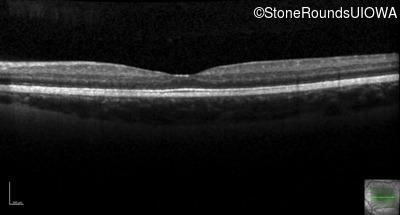

This 6 year old boy first experienced difficulty reading and seeing the blackboard at age 5.

| Age at visit: 6 years |